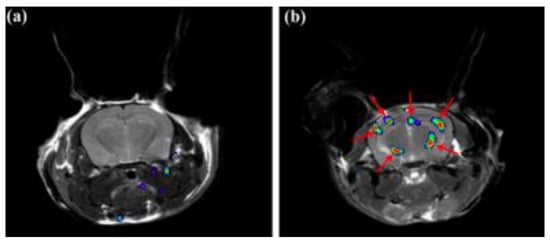

Further radiotracers include 18F-RO6958948 (RO-948), 11C-RO6931643 (RO-643), and 11C-RO6924963 (RO-963) and were all identified to show a high affinity to NFTs and have selectivity against Aβ in AD brains [78,79]. Of the three, 18F-RO-948 had a better signal-to-background ratio in AD patients than 11C-RO-643 and 11C-RO-963. In a human study, a higher uptake of 18F-RO-948 was observed in AD patients compared to healthy controls (Figure 7). [80]. 18F-MK-6240, a pyridine isoquinoline amine derivative, is a novel radiotracer that demonstrates a high selectivity for NFTs [81]. In vivo studies in humans show 18F-MK-6240 to have a high affinity to tau without any substantial off-target binding in the basal ganglia that would impede NFT detection [82]. 18F-JNJ64349311 (18F-JNJ311) has also been shown to have a high affinity for aggregated tau (Ki= 8 nM) and in vivo selectivity for tau over Aβ [83].

Figure 7.

(18F)RO-948 PET images overlaid on MRI on a healthy control (upper row) and an AD patient (bottom row). The increased uptake of (18F)RO-948 in the AD patient is associated with the binding to the hyperphosphorylated tau protein. [80]. Images are reprinted with permission of the publisher [80].